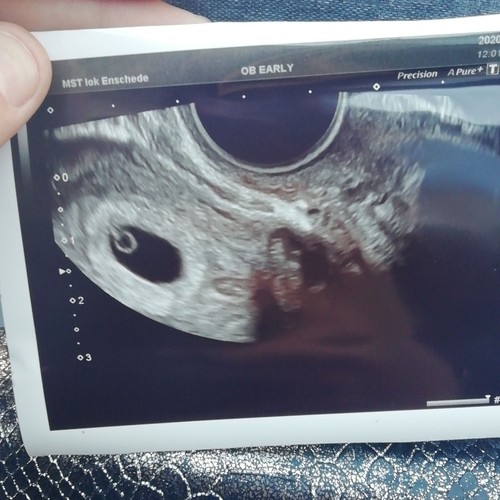

Ik zit met een klein dingetje, ik weet niet hoelang ik zwanger ben. Volgens de berekening van laatste menstruatie van 5 februari zou ik 6w2d zijn. Vorige week heb ik een inwendige echo gehad. Dus volgens de berkening 5w2d hier was alleen een duidelijke vruchtzak te zien. Door mijn PCOS weet ik dus niet mijn officele bevruchting. Nu krijg ik morgen weer een inwendige echo, ben zo bang dat er weer een lege zak te zien is..